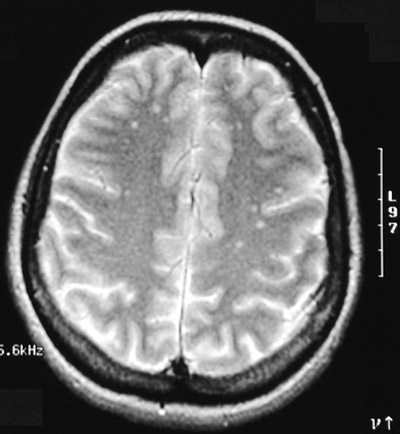

The T2 weighted MRI scans in axial view above and below demonstrate multiple small bright foci on the left as well as on the right that represent small areas of plaque formation in a patient with an exacerbation of multiple sclerosis.